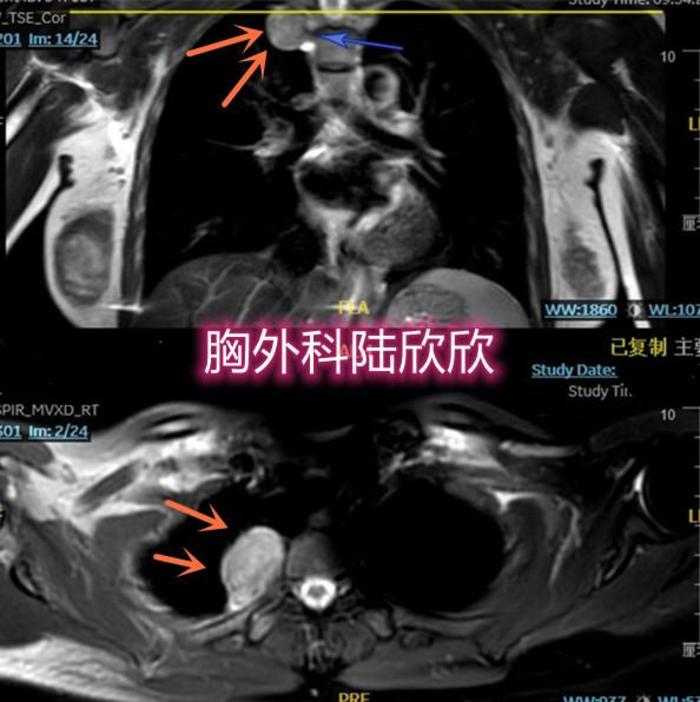

上图的核磁共振,可见右上纵隔一个肿物,位于后纵隔脊柱旁。椭圆形。肿块边界光滑,清楚,位于脊柱的椎间孔旁。磁共振的不同参数下,肿物的边界很清楚。与椎间孔的间隙清晰。看起来像是良性的神经鞘瘤